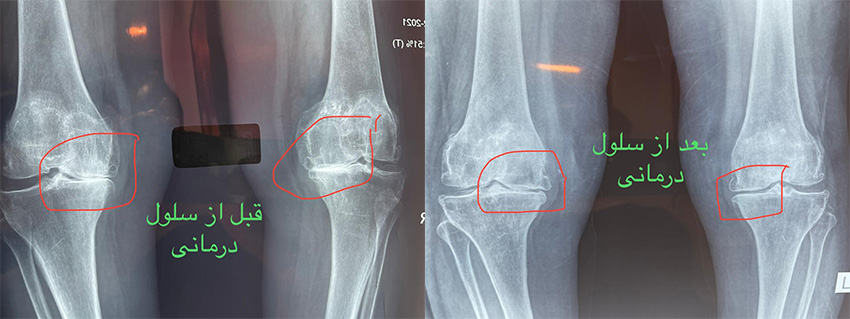

سلول درمانی زانو قبل و بعد